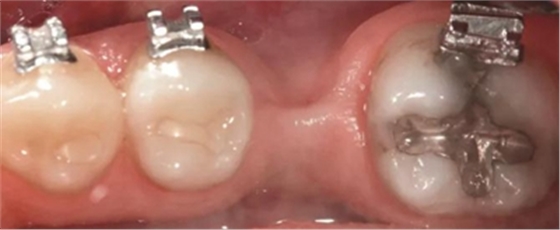

圖5a. 病例2中右下第一磨牙加速種植位點(diǎn)改建。初期排齊期間

圖5b. 術(shù)前臨床檢查